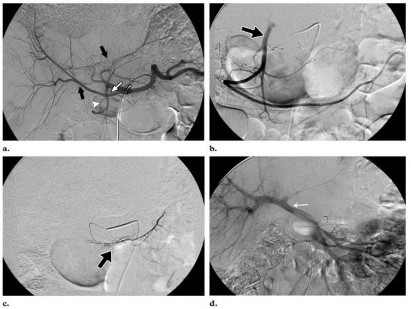

a) Chụp mạch gan trước điều trị

Chụp mạch đánh giá bản đồ mạch máu của gan cũng như mạch nuôi khối u gan trước điều trị, đánh giá khả năng di chuyển của các hạt phóng xạ vào các cơ quan có nguồn cấp máu từ động mạch thân tạng. Cân nhắc nút tắc dự phòng động mạch tá tụy, động mạch vành vị trái để giảm thiểu nguy cơ di chuyển các hạt phóng xạ vào các nhánh mạch này gây loét đường tiêu hóa trên, viêm tụy cấp

Sau đó luồn microcatheter vào vị trí dự kiến bơm hạt phóng xạ, bơm

99mTc – MAA liều 5mCi.

Hình 2.1: Hình ảnh nút bằng coils động mạch vị tá tràng và động mạch vành vị phải trước khi bơm dược chất phóng xạ vào nhánh mạch nuôi u.

(Nguồn Mai Trọng Khoa (2012), Y học hạt nhân, Nhà xuất bản Y học Hà Nội)